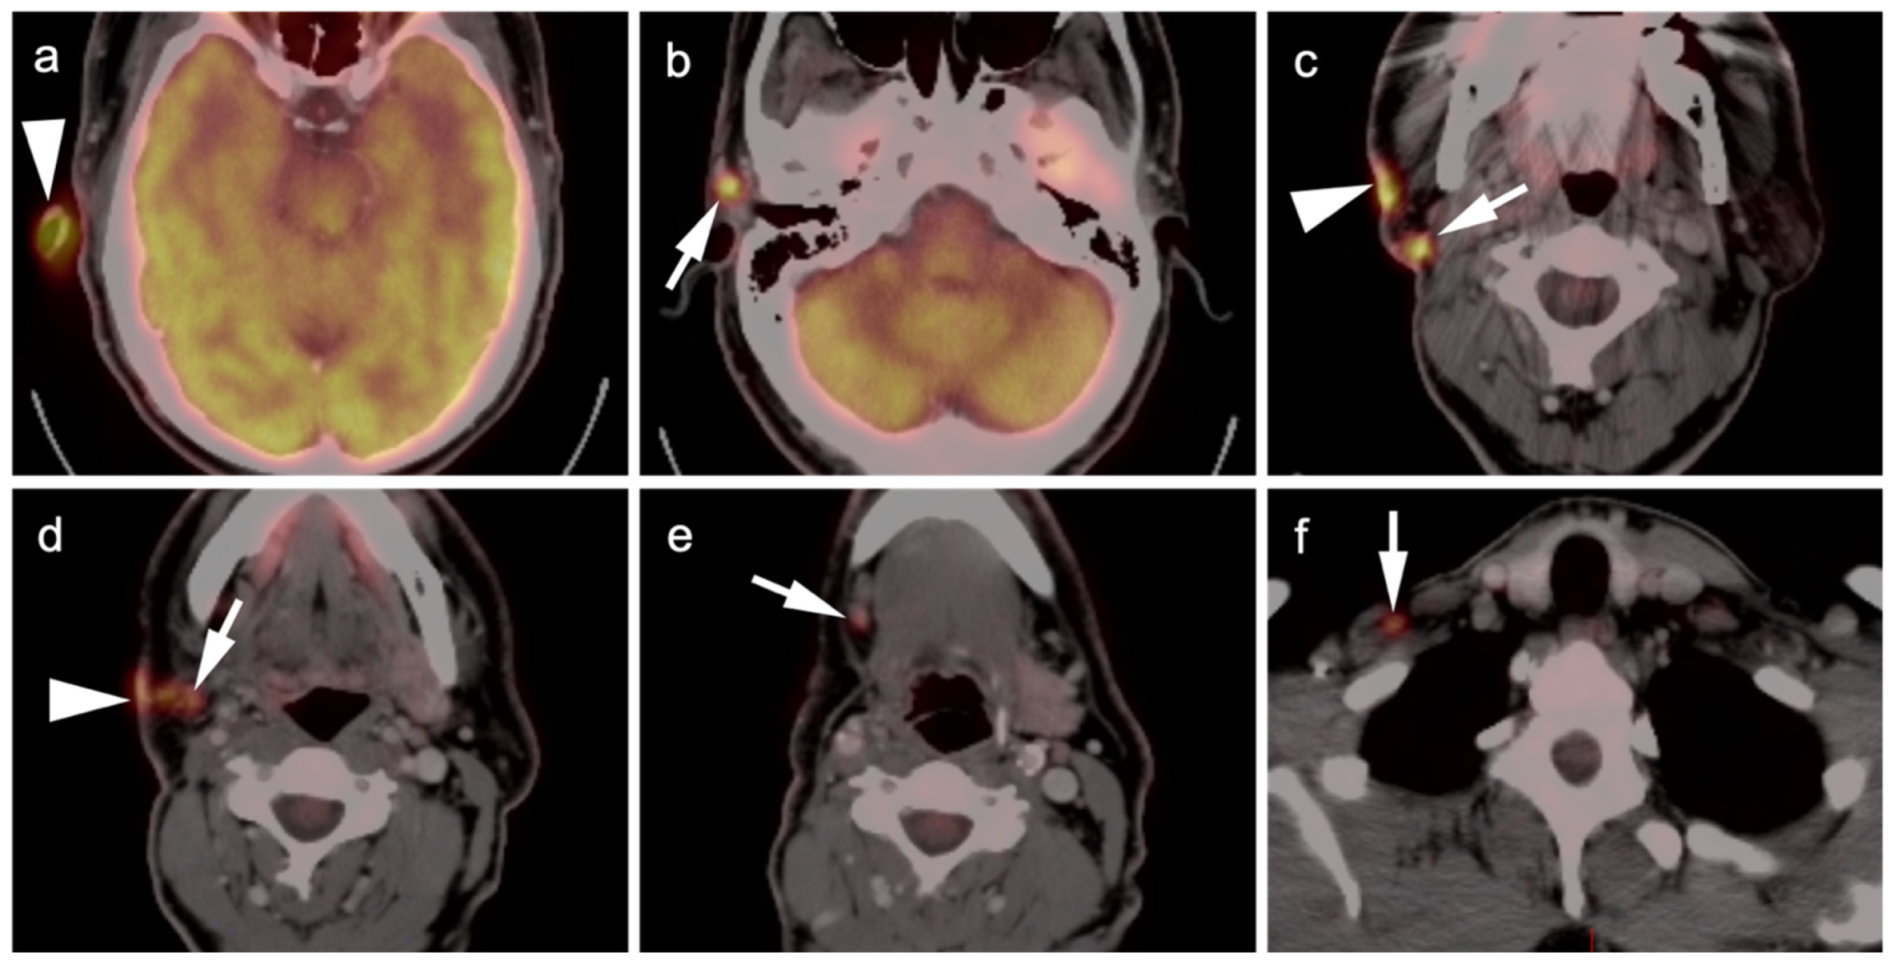

2.3.1. Cutaneous Melanoma

2.3.3. Mucosal Melanoma